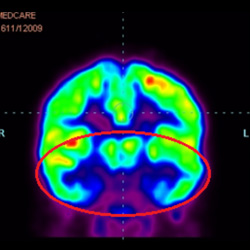

細(xì)胞治療后,藍(lán)色和黑色區(qū)域減少,并且看到更活躍的區(qū)域。這表明損傷減少并改善了大腦功能。

細(xì)胞治療前 PET CT 掃描顯示神經(jīng)組織中的藍(lán)/黑色區(qū)域,表明腦癱引起的大腦損傷。

這證明細(xì)胞療法是治療腦癱兒童安全有效的方法。細(xì)胞療法可以更新大腦損傷的核心,并且可以通過 PET CT 掃描來監(jiān)測大腦的改善情況。這些細(xì)胞療法與標(biāo)準(zhǔn)治療一起促進(jìn)腦癱兒童的生長和改善。